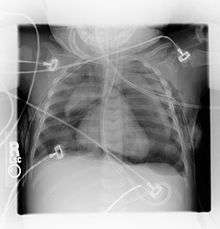

Pneumomediastinum is uncommon and occurs when air leaks into the mediastinum. The diagnosis can be confirmed via chest X-ray showing a radiolucent outline around the heart and mediastinum or via CT scanning of the thorax.